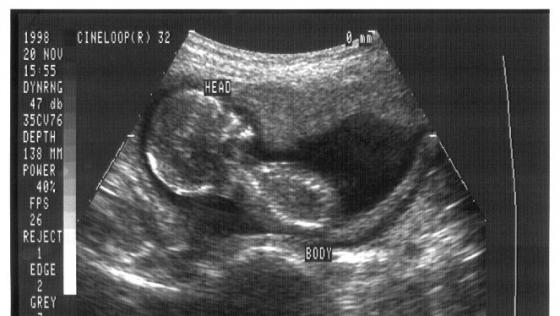

To add insult to injury, even science seems to be turning against abortion partisans. “modern prenatal imagery gives abortion opponents a new way to make their case.”